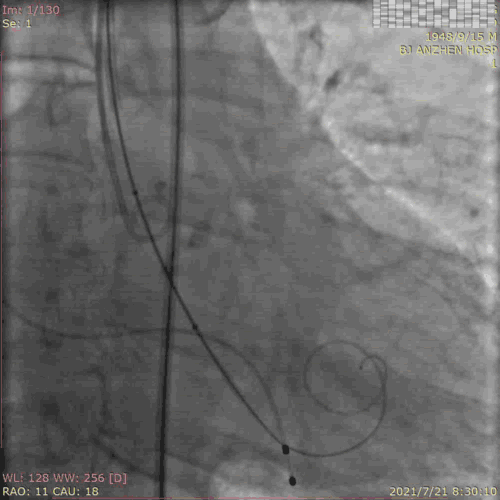

TAVR过程:患者局麻后,植入临时起搏器,穿右股动脉送入23mm球囊预扩张病变,左、右冠状动脉未受明显影响,决定直接植入爱德华SAPIEN 3 26mm 球扩式瓣膜,选择标准位进行释放。